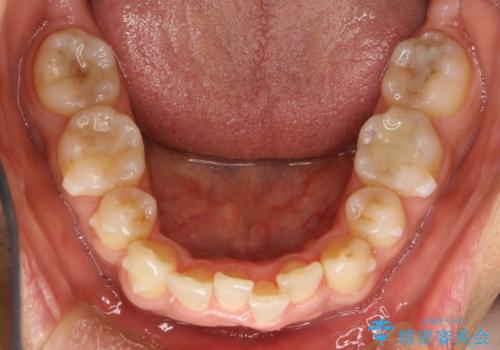

- 以前、上下左右4本抜いてワイヤー矯正をしていた方で、後戻りで下の前歯のガタガタを気にして来院されました。

マウスピース矯正にて、下の歯はIPR(歯と歯の間を削る)を入れることでガタガタの改善、咬み合わせの深さも改善をはかる治療計画をたてました。

歯と歯の間を削って隙間を作って矯正をしています。

保定装置(後戻り防止のための装置)は、基本的にはマウスピースタイプをお渡ししているのですが、患者様のご希望で取り外ししないタイプを希望されたので、前歯の裏側を細いワイヤーで固定(ボンディングリテーナー)を作成しています。